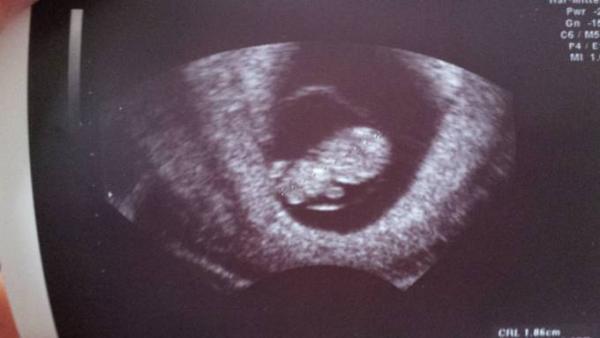

Hallo ihr Lieben, Ich hatte gerade nochmal einen Termin und es ist alles Bestens. Der Teddy ist auf den Tag zeitgerecht entwickelt (8+5) und hat uns zugenickt Ich bin total verliebt Hier das Bildchen

Bild zu FA-Termin - Forum für Juli - Mamis